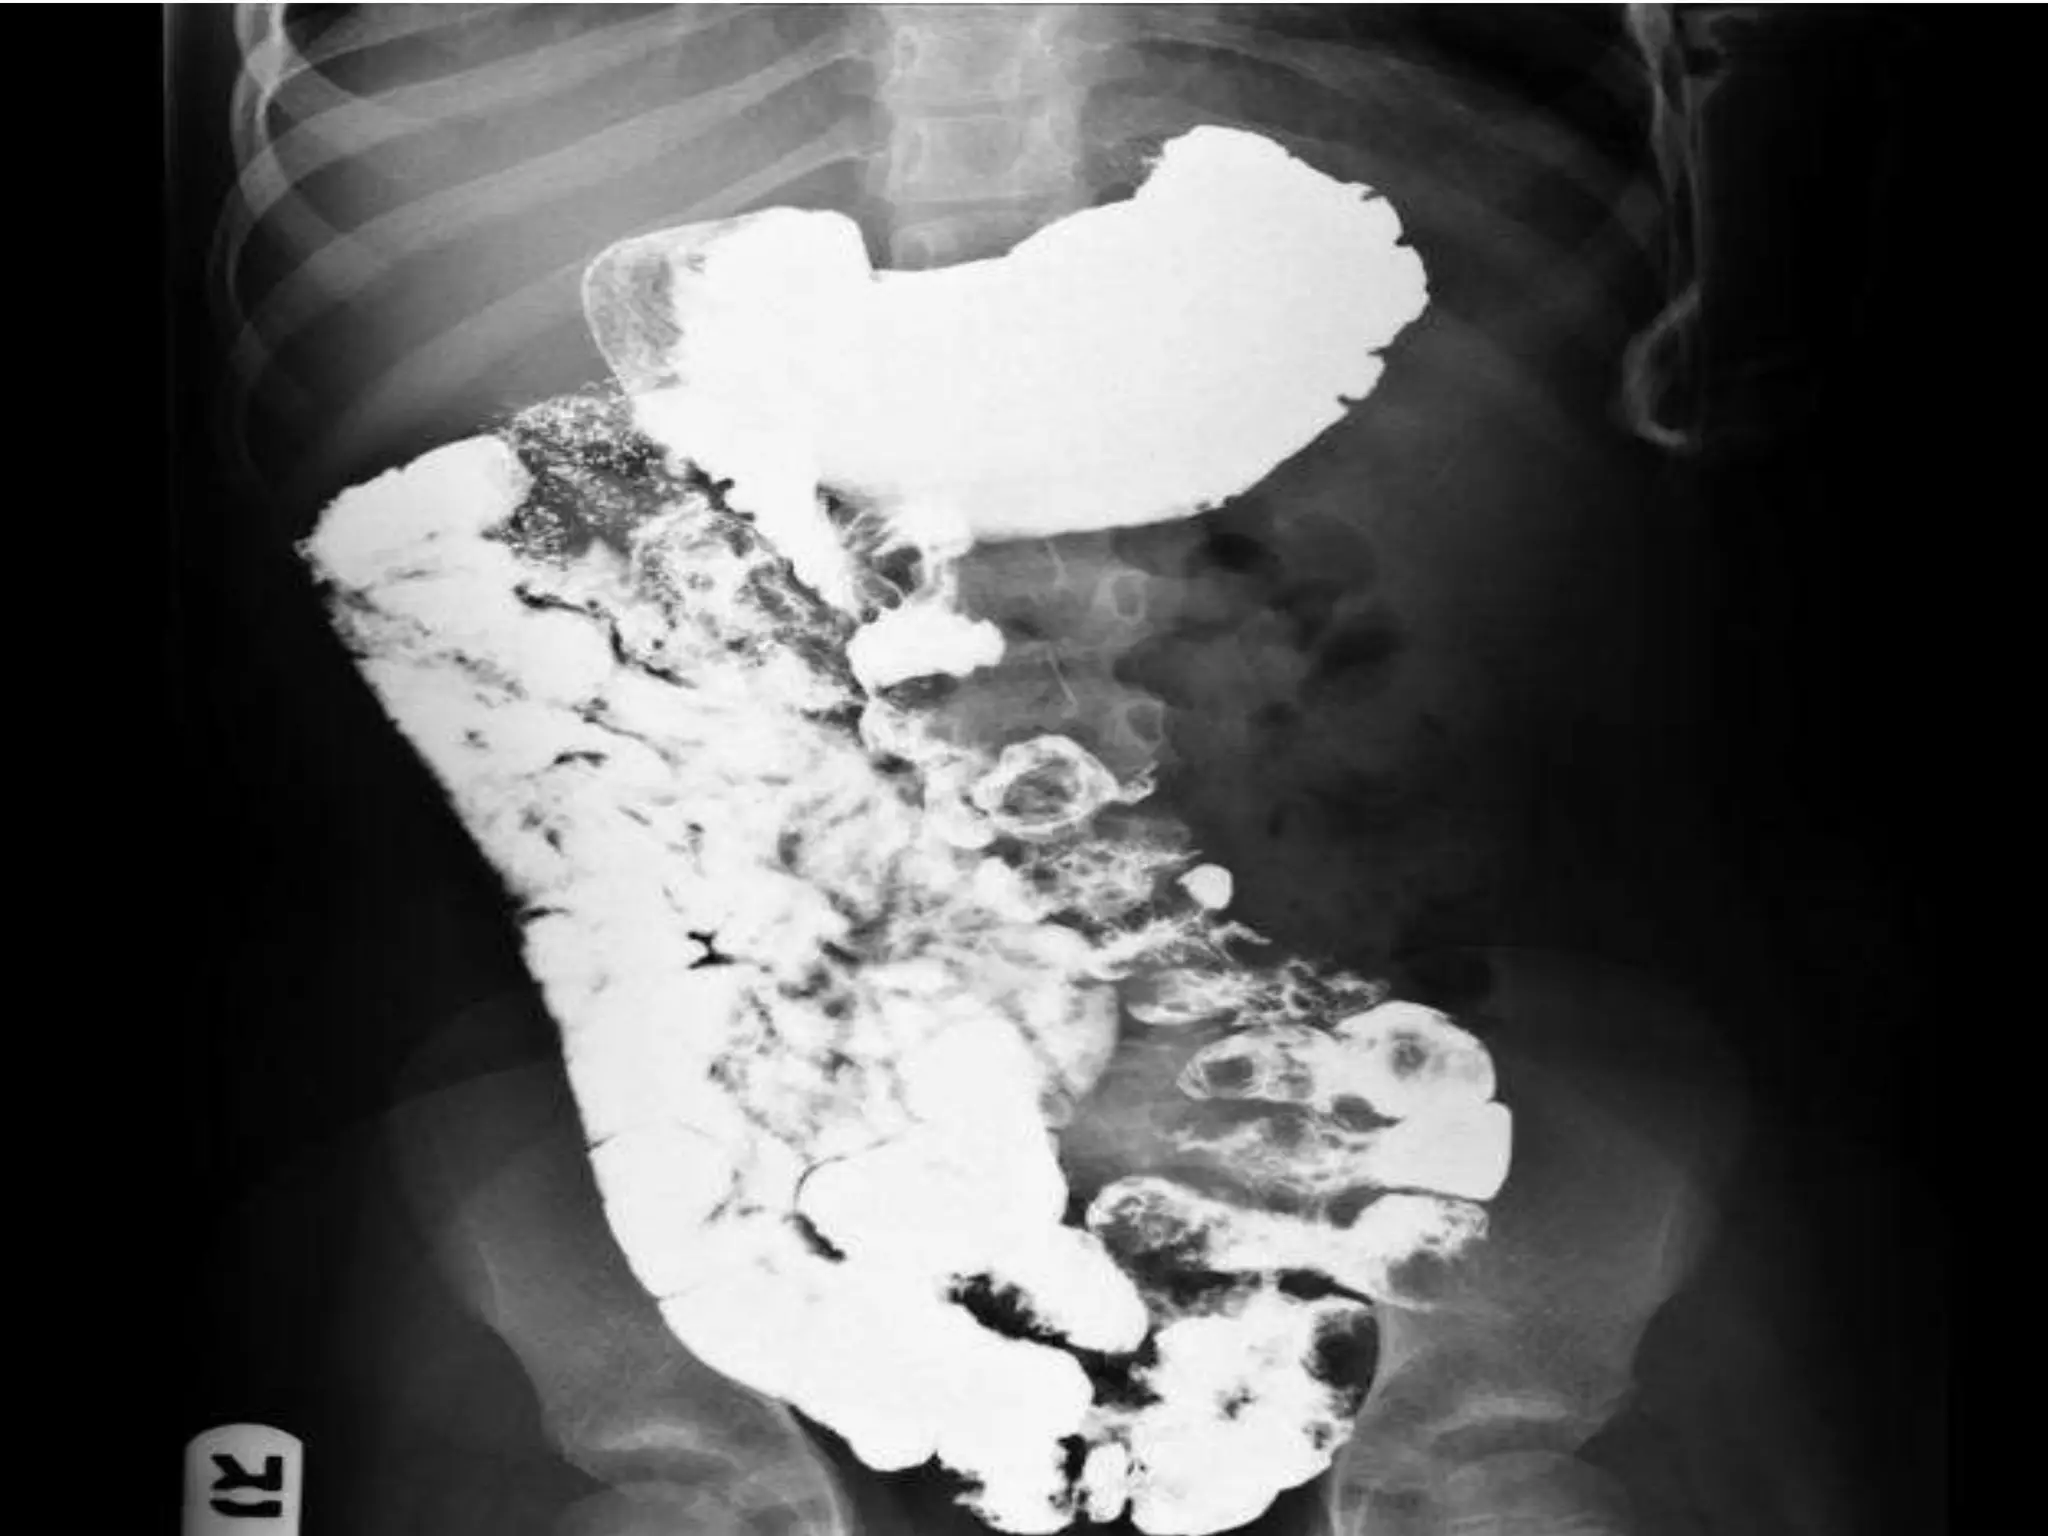

DIAGNOSIS

• Plain X-Ray.

• Doppler study.

• Upper contrast study.

• CT- scan.

DIAGNOSIS • Plain X-Ray. •Doppler study. • Upper contrast study. • CT- scan.